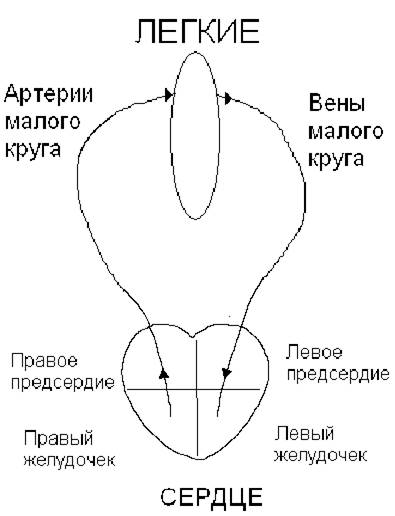

Жидкая или полужидкая пищевая кашица, имеющая резко выраженную кислую реакцию, переходит из желудка в тонкий кишечник, где подвергается дальнейшему перевариванию под действием кишечного сока, желчи и сока поджелудочной железы, которые имеют уже щелочную реакцию (рН 8,5 – 9,0).

Под влиянием этих соков в тонком кишечнике происходит окончательное расщепление почти всех пищевых веществ и всасывание продуктов расщепления в кровь и лимфу.